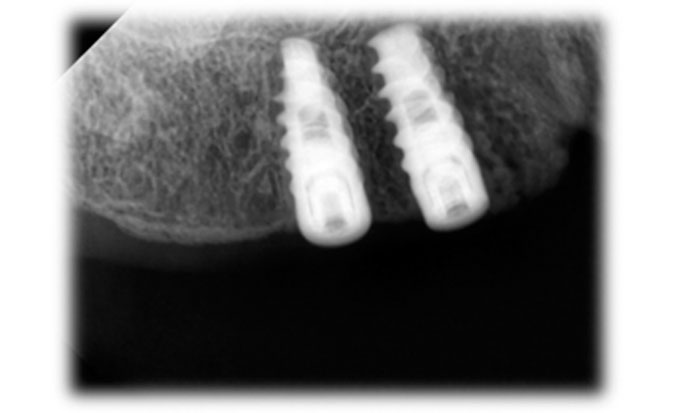

Guided Implant Surgery involves the use of advanced 3D imaging and computer-aided design (CAD) to plan the exact placement of dental implants. This meticulous planning process allows our dental specialists to visualize the patient’s oral anatomy in great detail, ensuring the implants are placed in the most ideal position for both functionality and aesthetics. The procedure is tailored to each patient's unique needs, ensuring a personalized treatment plan.

These technique assures that the implant is precisely placed without any damage to nerves, vessels and wouldn't perforate maxillary sinus too.